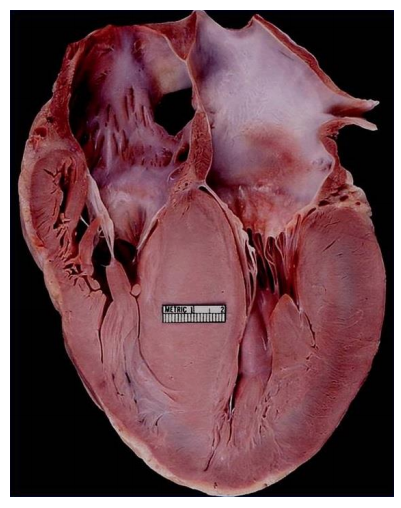

A 19-year-old man with no previous medical history collapses suddenly on the basketball court and dies, despite aggressive resuscitation attempts. Interestingly, the man’s uncle died in his early 20s under similar circumstances. An autopsy is performed.

A. What is the diagnosis?

B. What gross finding is the basis for this diagnosis?

C. Name 3 consequences of this disease:

D. What percentage of cases are due to a genetic abnormality?

E. In familial cases, what is the most common inheritance pattern, and what genes most commonly harbor mutations?

A. hypertrophic cardiomyopathy

B. septal hypertrophy - asymmetric, LVH

C. HF, exercise intolerance, sudden death

D. 100%, though not all are inherited - about 50/50

E. autosomal dominant, penetrance varies, all affect sarcomeres